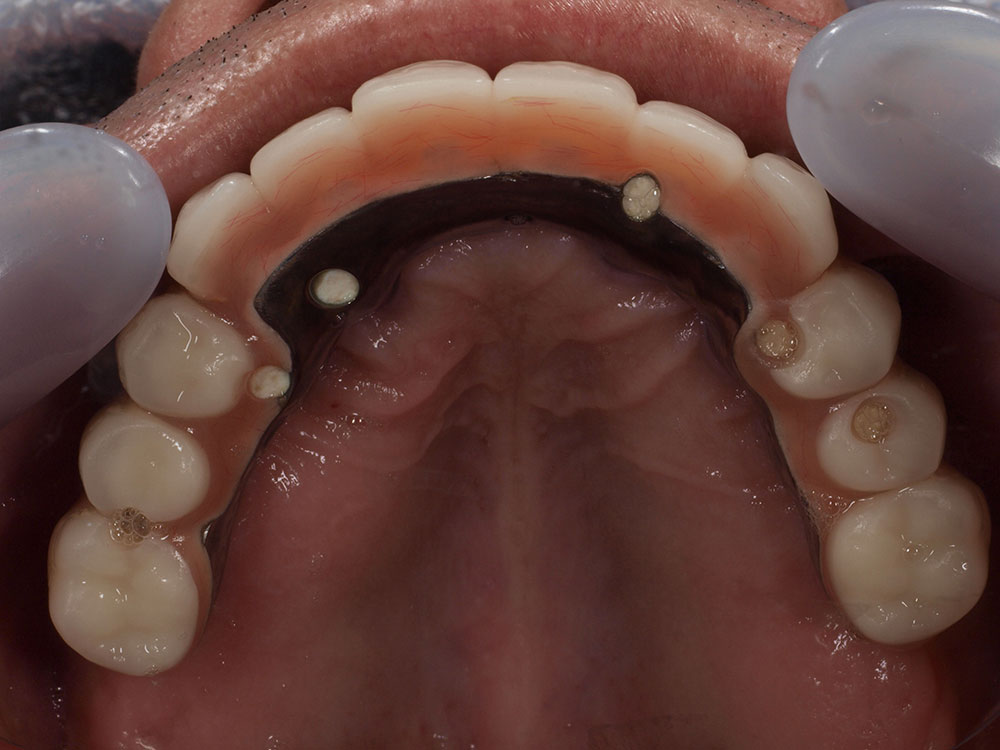

- 主訴

- 入れ歯が気持ち悪く、しっかりと食べれない。本当につらい。美味しく食べて、豊かな人生を過ごしたい。

- 処置内容

- 上顎6本(オールオン6)

- 治療費用

- 上顎350万円(税込)

- 治療期間

- 上顎1年(仮歯まで8か月)/約10回

- リスク

- 上部構造物、仮歯の破折、術後の腫れ(3日)、人工歯根脱落のリスクがあります